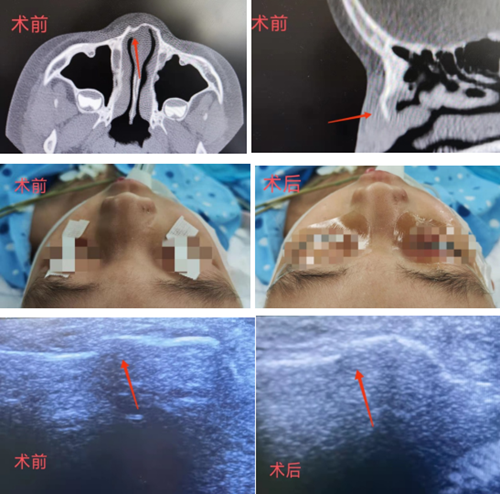

一天,強(qiáng)強(qiáng)在家中玩耍時(shí),不小心撞到墻上。一陣酸痛感襲來,強(qiáng)強(qiáng)“哇”的哭出了聲,鼻子當(dāng)場(chǎng)出血,不一會(huì)兒變得青紫腫脹。強(qiáng)強(qiáng)父母趕忙帶孩子趕到青島婦女兒童醫(yī)院耳鼻喉科就診。接診醫(yī)生結(jié)合CT檢查結(jié)果確認(rèn)孩子為右側(cè)鼻骨骨折,需要通過手術(shù)復(fù)位來解決。

耳鼻喉科醫(yī)生耐心和強(qiáng)強(qiáng)媽媽解釋,可以在高頻超聲引導(dǎo)下進(jìn)行鼻骨骨折復(fù)位。高頻超聲好比醫(yī)生的“眼睛”,這樣手術(shù)可以實(shí)現(xiàn)可視化,克服了傳統(tǒng)復(fù)位的弊端,更精準(zhǔn)、可靠。這樣一解釋,解除了孩子父母的擔(dān)心,表示接受這個(gè)治療方案。

完善相關(guān)檢查后,耳鼻喉科團(tuán)隊(duì)為強(qiáng)強(qiáng)進(jìn)行了鼻骨復(fù)位。在超聲引導(dǎo)下,手術(shù)醫(yī)生應(yīng)用復(fù)位器挑起游離骨片進(jìn)行復(fù)位調(diào)節(jié),將油紗條填塞在右側(cè)鼻腔內(nèi)起到支撐作用,手術(shù)順利完成,復(fù)位后的鼻子外觀無畸形。目前,強(qiáng)強(qiáng)已康復(fù)出院。